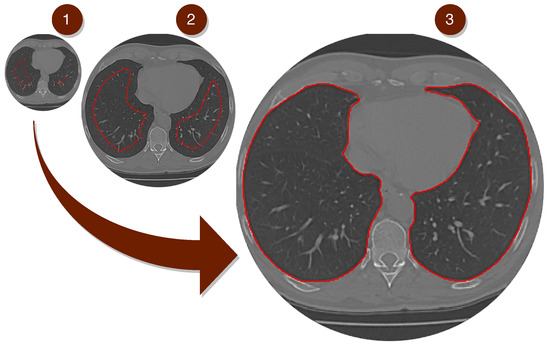

The Equations (4) direct the expansion to the edges of the lung, indicating which direction this movement should be in, as shown in the Figure 5.

Figure 5.

The Figure above shows the segmentation of the lung using our Composite Method, based on deep learning combined with the Parzen window method through Transfer Learning.

In RESULT, after a series of expansions at the edges, the movement loses speed and energy, as the calculations stabilize. Then after fixing the edges of the lungs, the segmented region is extracted by concatenating the edges and their internal area, as shown in RESULT image.

The pulmonary region can be obtained by subtracting the region segmented by the original image of the exam, as shown in the Figure 6, where it can be better analyzed visually.

Figure 6.

It presents the model’s segmentation differently; inline 1, the lung’s CT images are shown without segmentation methods. Inline 2, we offer the images already segmented by the proposed method. Inline 3, the images were enlarged for better visualization of the results. Inline four, the segmentation served as a basis for lung extraction for a better visual analysis of our model’s final result.